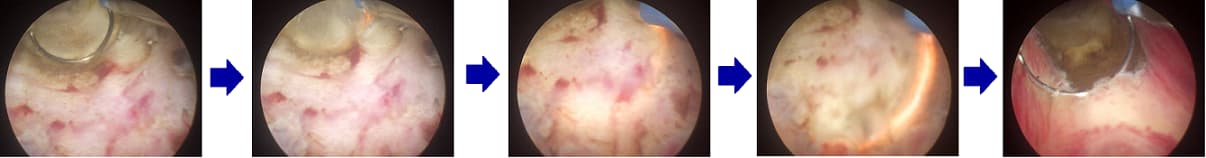

Công nghệ Vessel Sealing được áp dụng rộng rãi trong nhiều loại phẫu thuật, đặc biệt phẫu thuật tuyến tiền liệt và phẫu thuật T.U.R.P (cắt đốt nội soi qua niệu đạo). Với khả năng cầm máu tốt, dao mổ ZEUS PRIME giúp thao tác phẫu thuật diễn ra nhanh hơn và an toàn hơn.